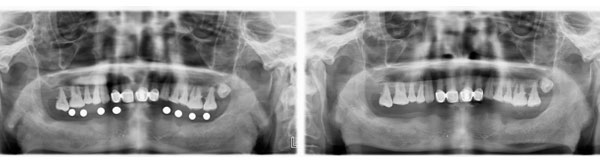

患者下半口多颗牙种植修复